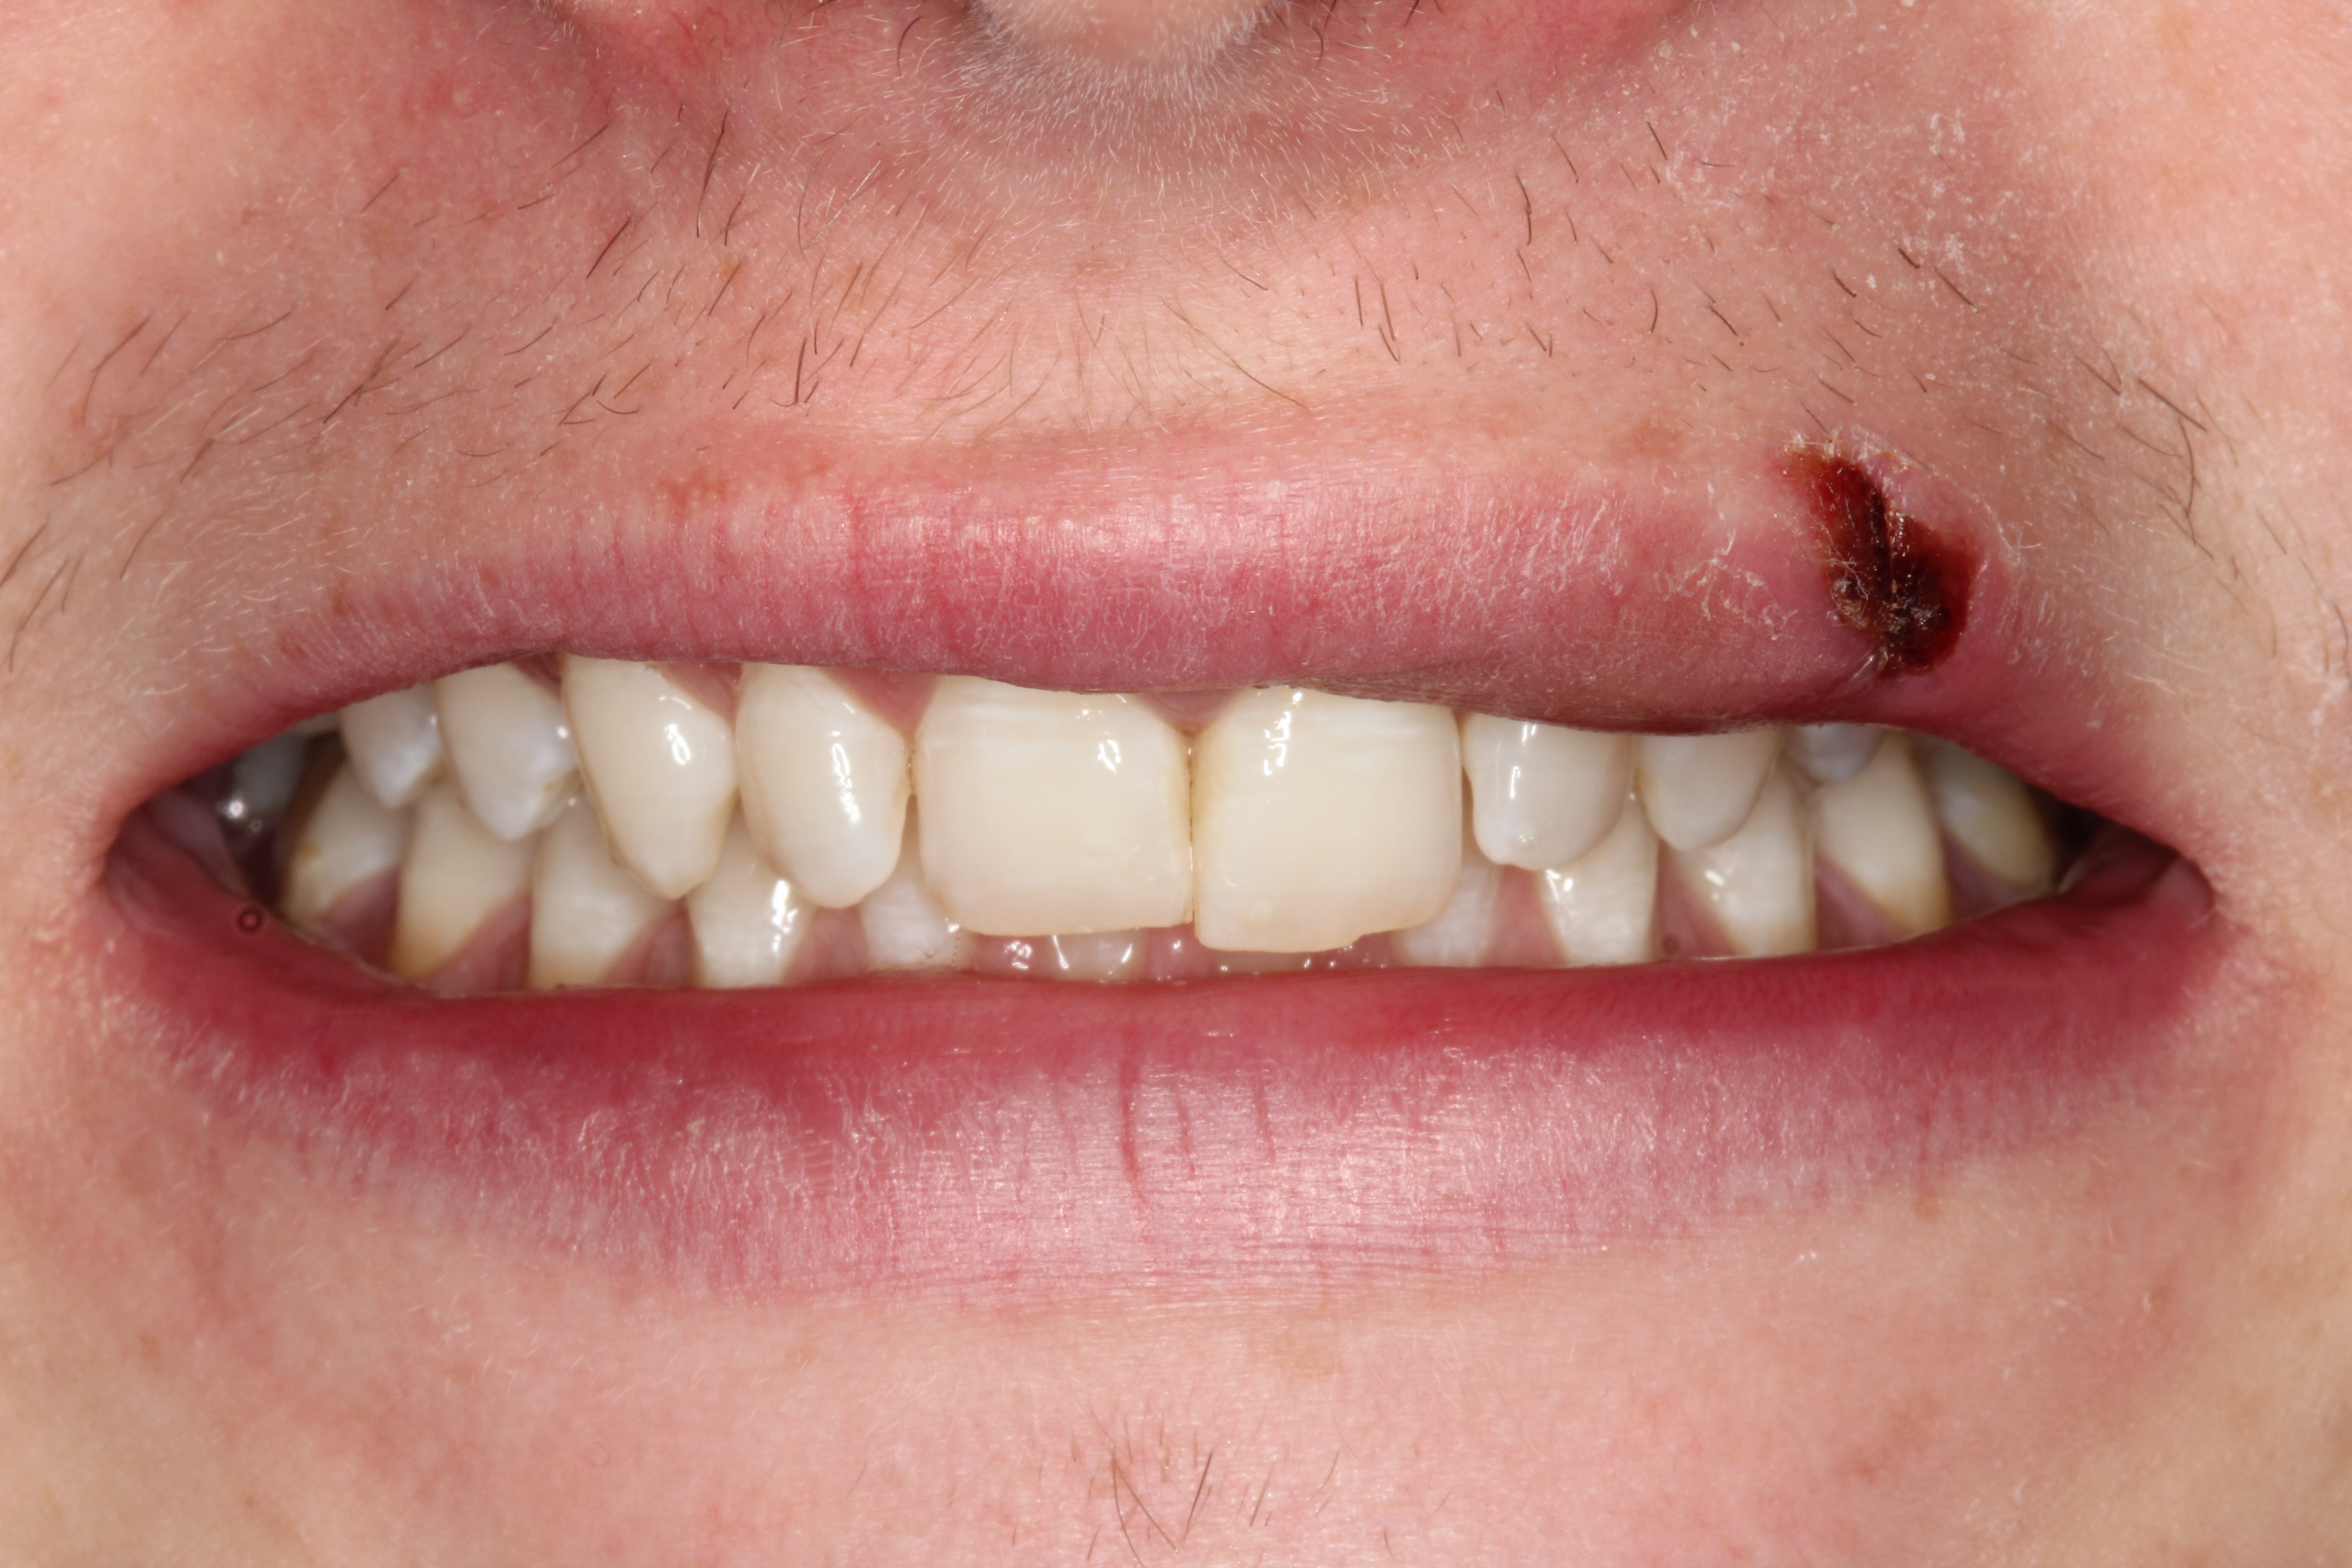

A young man presented with a fractured maxillary left-central incisor on a Monday morning after a Saturday evening discussion that did not end well (Figure 1). Visual oral examination and palpation of the structures revealed mobility of 3+, pain on palpation and percussion, a thick soft-tissue profile, and a low lip line. Gingival zeniths were irregular, there was a class II division 2 deep bite, and the periodontium was healthy overall (Figure 2 through Figure 4). Radiographs requested at the time of the initial visit were periapicals, panoramic, and CBCT images (Figure 5 and Figure 6). After all images and information were reviewed and the extent of his injury was discussed, the patient was presented with the following options: removable prosthetics, fixed partial denture, extract and do nothing, or extract and place a dental implant with bone augmentation.

Reviewing the CBCT images with the patient proved beneficial because he was able to clearly see the complete fracture of his tooth in the apical third of the root (Figure 6). Figure 5 represented what is a common radiograph in most dental offices, but it was not clear enough to diagnose a root fracture of this nature. The patient understood that the prognosis was poor and that the long-term restoration he wanted would mimic nature and be maintainable like natural dentition. The visual examination and photographs provided a basis for subsequent dental therapy and a definitive treatment plan for the future. The patient decided to move forward with tooth extraction, grafting, and immediate dental-implant placement with a screw-retained provisional out of occlusion.